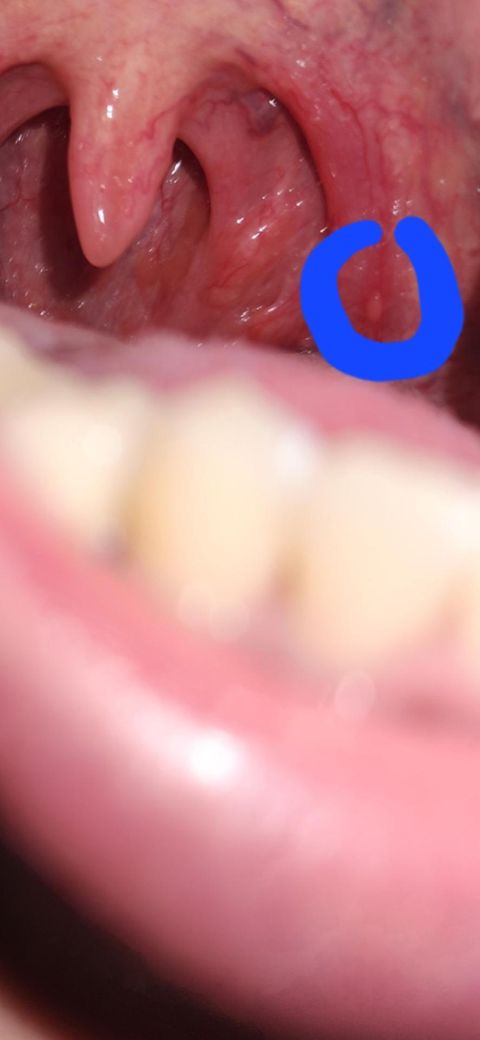

입안에 난 돌기에 대해서 의견여쭙니다

후레쉬로 비추다가 우연히발견했는데

파란부분 작게 튀어나와있는데

특별한증상은 없는데

그냥둬도될까요? 아니면 병원에 가봐야할가요?

40대 남성분께서 입안에 생긴 돌기 때문에 걱정이 많으시겠네요. 입안에 생긴 돌기는 다양한 원인에 의해 발생할 수 있으며, 특별한 증상이 없더라도 주의 깊게 관찰하는 것이 중요합니다. 만약 크기가 커지거나 통증, 출혈 등의 증상이 나타난다면 병원에 방문하여 정확한 진단을 받는 것이 좋습니다. 하지만 크기 변화가 없고, 특별한 증상이 없다면 경과를 지켜봐도 괜찮을 수 있습니다.

하지만 인터넷 정보만으로는 정확한 판단이 어려우므로, 불안하시다면 가까운 이비인후과나 구강내과를 방문하여 전문의와 상담해보시길 권해드립니다. 전문의는 구강 검사를 통해 돌기의 원인을 파악하고, 필요한 경우 추가 검사를 진행하여 적절한 치료 계획을 세울 수 있습니다. 건강한 구강 관리를 통해 걱정을 덜고 편안한 일상을 보내시길 바랍니다.

평소에 입안을 매일 보면서 살지는 않으므로 저정도의 돌기는 있다가 없다가 합니다. 현재 통증도 없기 때문에 당장 급한것은 아니겠으나, 통증 동반된다거나 크기가 커진다면 이비인후과 진료 가보시는게 좋겠습니다